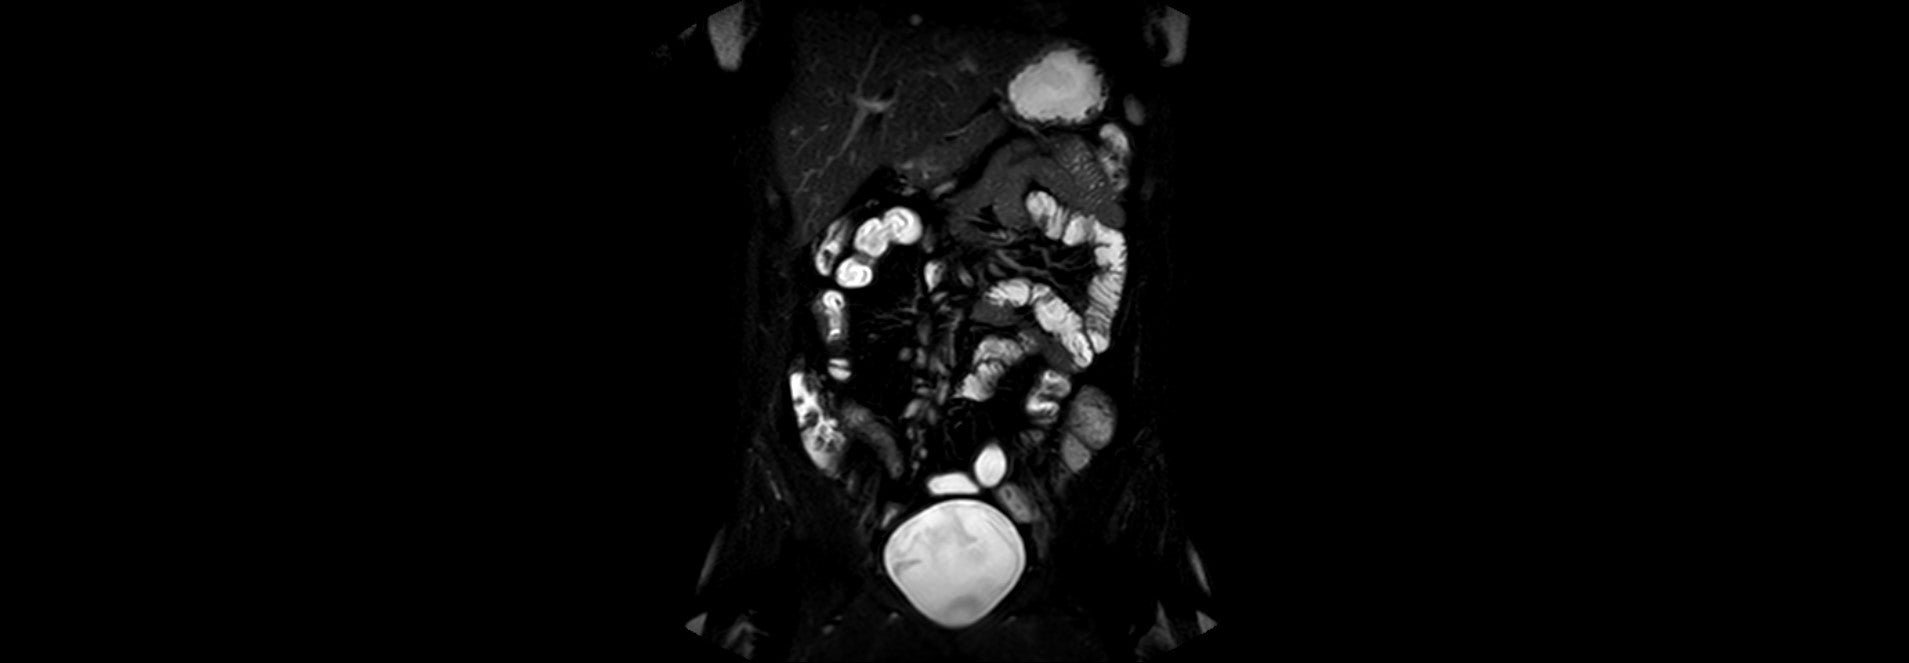

MR enterografie ze dne 03.08.2023 - T2 vážený obraz s potlačením tuku

Klinika radiologie a nukleární medicíny FN Brno

Tato kazuistika se zabývá případem mladého muže, nyní ve věku 27 let, u kterého byla v roce 2019 diagnostikována Crohnova nemoc. Primárně byl léčen v té době doporučovanými aminosalicyláty a později azathioprinem, na kterém došlo v únoru 2023 k relapsu onemocnění s multisegmentálním postižením s prestenotickými dilatacemi a zánětlivým pseudotumorem (dle CT vyšetření břicha), které vyžadovalo zavedení enterální výživy a biologické terapie. Pacient byl k další léčbě přeložen na naše pracoviště. V první linii byla použita anti-TNFα terapie infliximabem, na které došlo k postupné úplné regresi aktivity a normalizaci fekálního kalprotektinu. Vzhledem k nutnosti rozsáhle resekce střevních kliček při chirurgickém výkonu s rizikem následného rozvoje syndromu krátkého střeva byl nadále indikován konzervativní postup, pacient byl ale plně realimentován bez pasážovacích potíží.